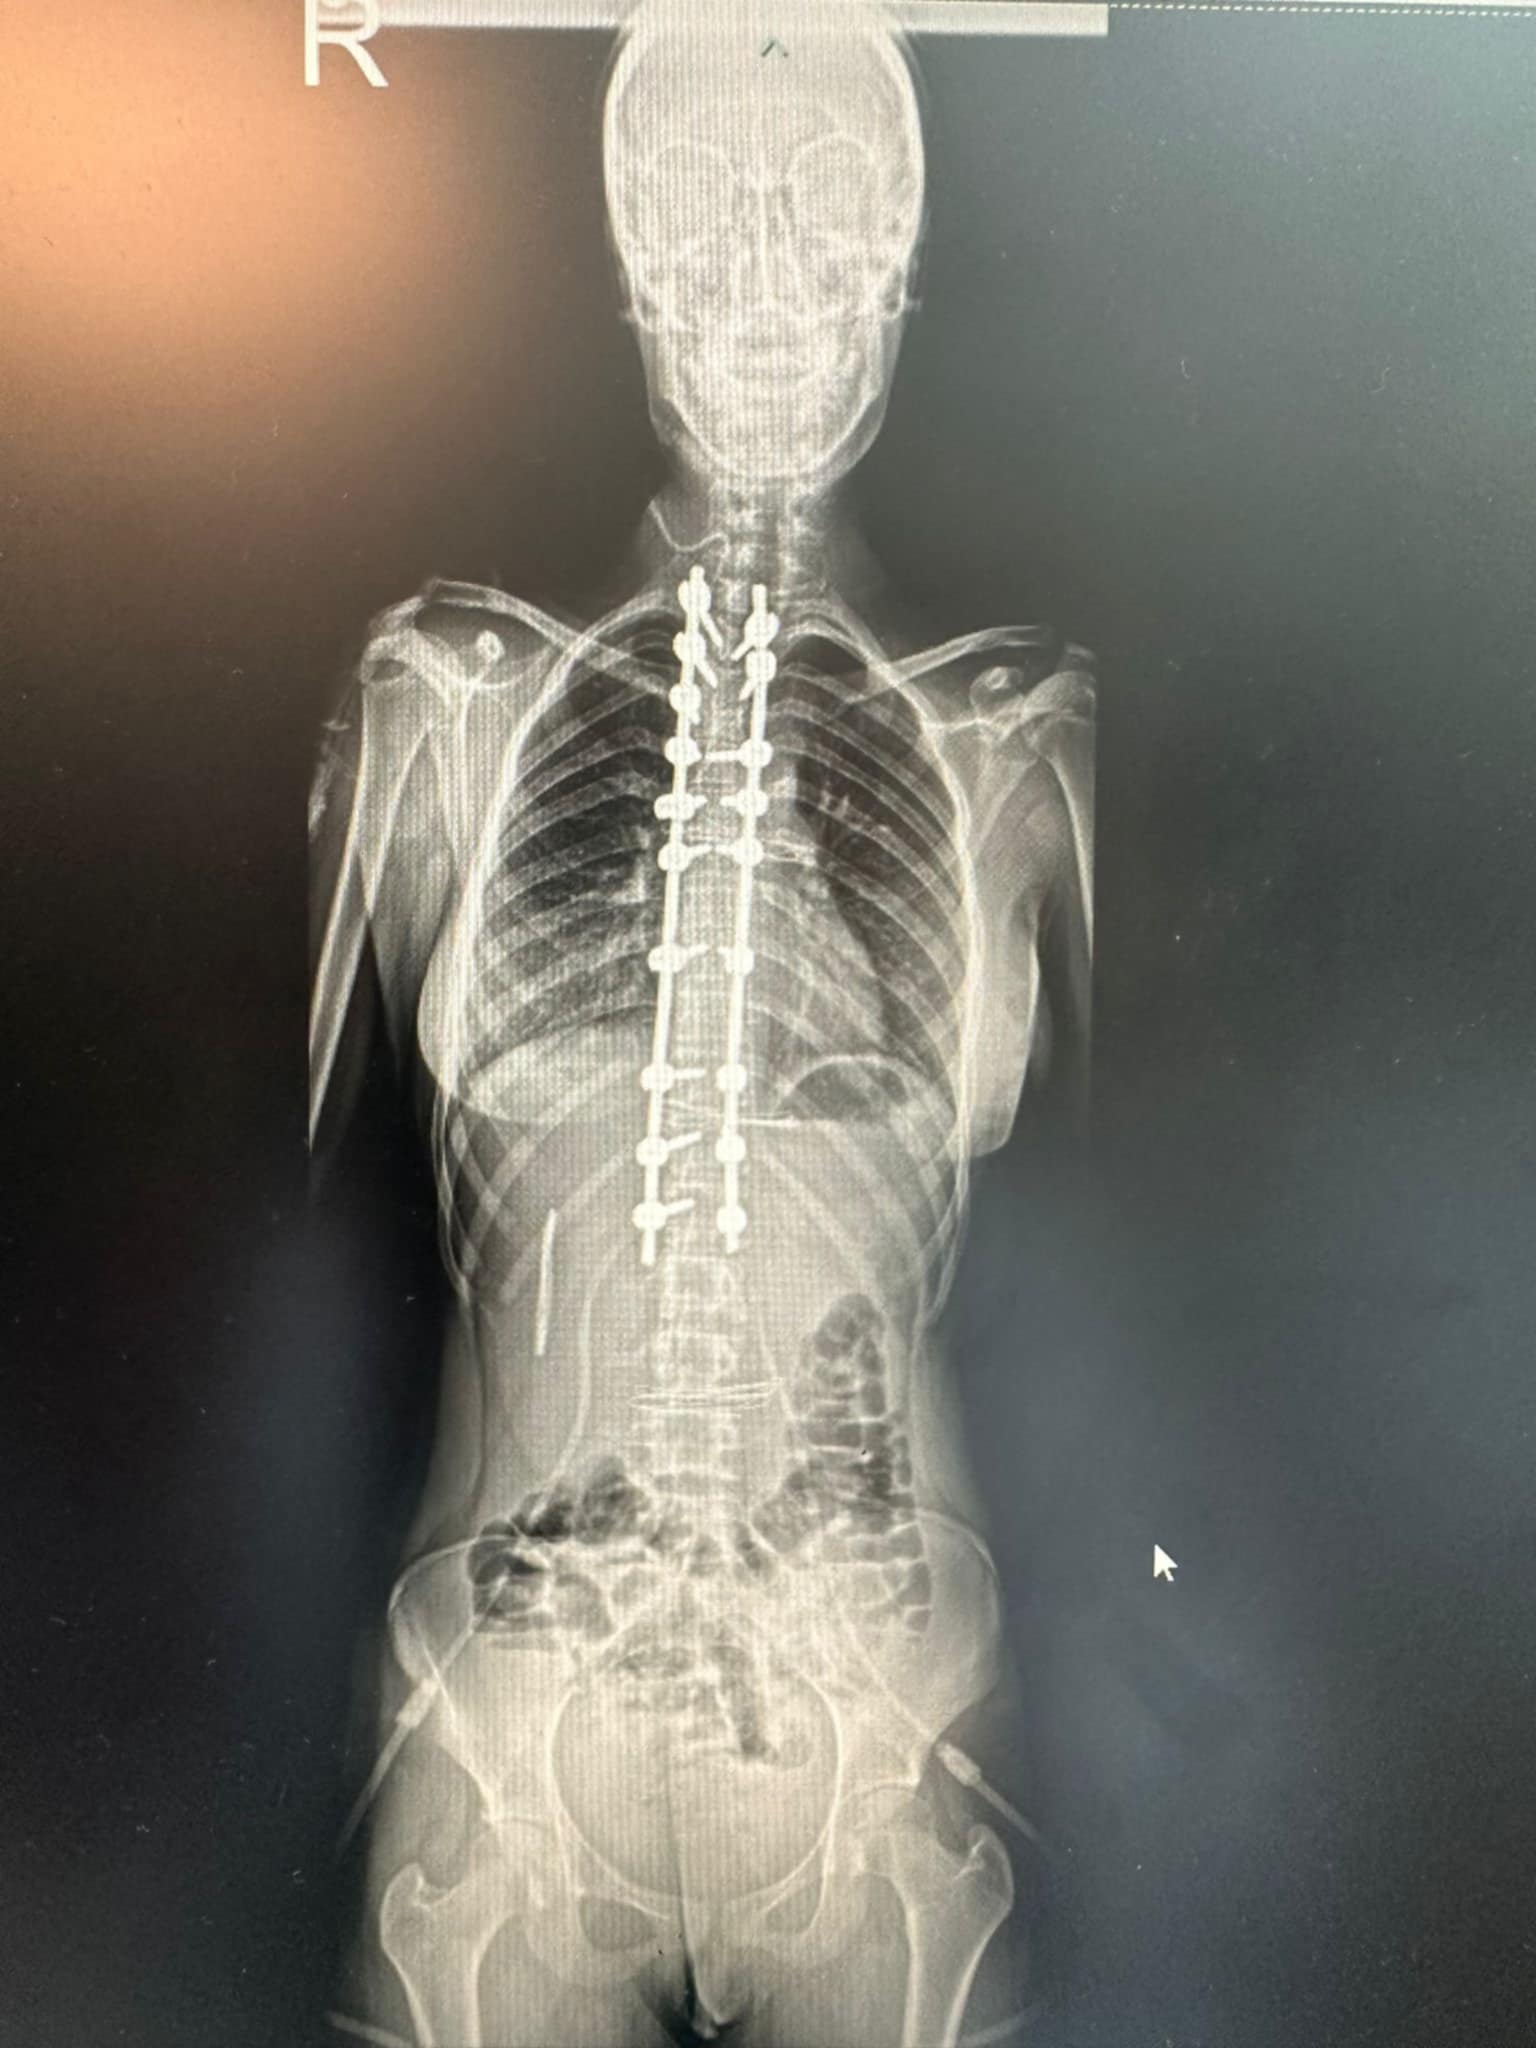

Andreea Crecea merge astăzi cu spatele drept și cu zâmbetul pe buze.

Operația de scolioză a fost un succes, iar visul ei de a trăi fără durere a devenit realitate!